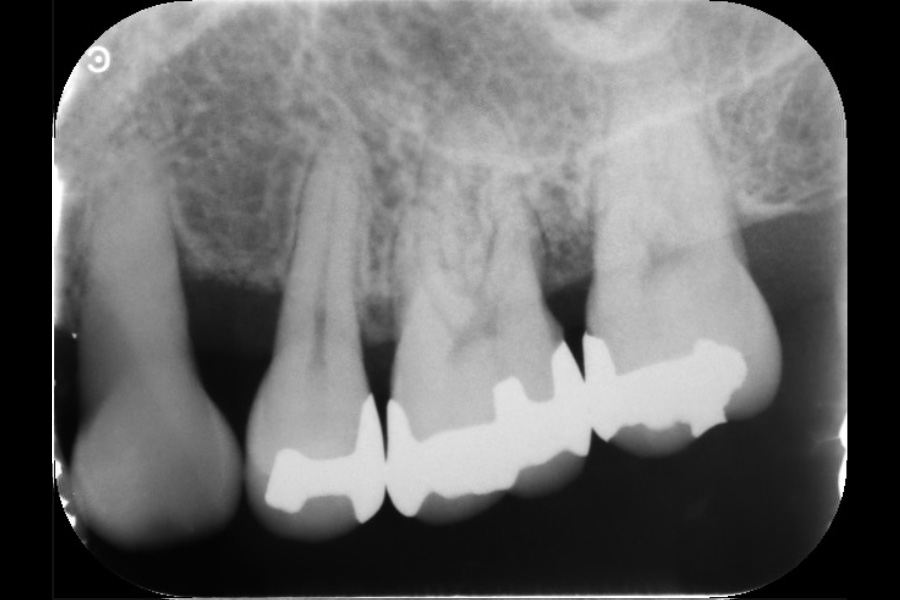

左上奥歯の歯ぐきが腫れて、噛むと痛い

【歯周組織再生療法】

- 主訴

- 左上奥歯の歯ぐきが腫れて、噛むと痛い

- 期間

- 再生療法から再評価まで6か月

- 費用

- ¥220,000(税込)

- 治療内容

- 左上4遠心と左上6近心に垂直性骨吸収が認められたためエムドゲインと骨補填材を用いて歯周組織再生療法を行った

- 治療に伴うリスク

- 歯肉退縮、知覚過敏